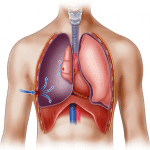

Tràn khí màng phổi (Pneumothorax) là hiện diện của khí bất thường trong khoang màng phổi, có thể 1 hoặc 2 bên. Có thể tạo áp lực dương trong khoang màng phổi do cơ chế van, khí đi vào mà không thoát ra được, gọi là tràn khí màng phổi áp lực, kèm với di lệch trung thất sang bên đối diện…